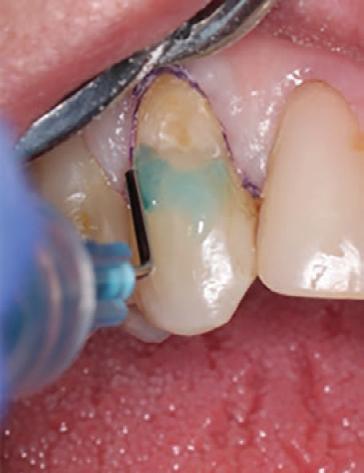

Etching and Bonding